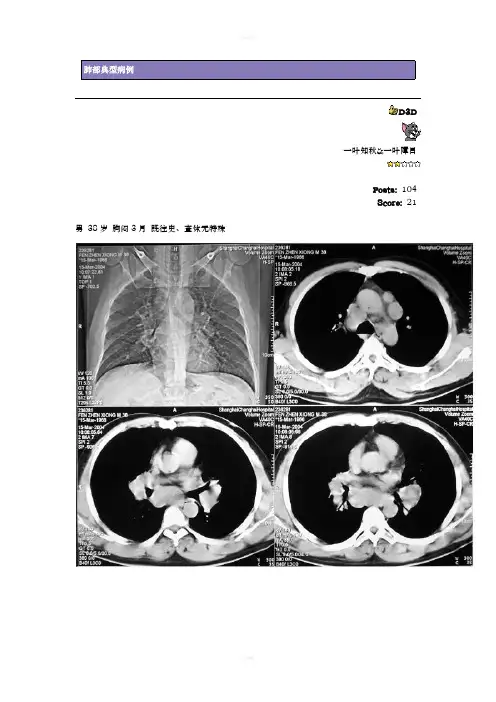

肺部典型病例D3D一叶知秋&一叶障目Posts:104Score:21 男38岁胸闷3月既往史、查体无特殊男38岁胸闷3月既往史、查体无特殊病理E C T结果doctorwangwq顺其自然丁香园主任Posts:2764Score:802双侧肺门区、纵隔内示有多发性肿大淋巴结影,两侧对称性分布,两肺门对称性肿大呈土豆块状改变,双肺示肺纹理增强,实质内未见异常。

结合病理报告首先考虑结节病(I期改变)。

分析:本病是一种原因不明的全身性疾病,病理学上为非干酪性上皮样慢性肉芽肿、临床上呈慢性经过,好发于30-40岁的女性,可侵及全身各器管,常见于肺部和淋巴结,引起肺门淋巴结肿大和肺部浸润性改变。

X线平片上,Siltzbach等将其分为3期,I期:肺门淋巴结肿,不伴有明显的肺部改变;II期:肺门淋巴结肿大伴肺组织浸润;III期:肺门淋巴结不肿大,仅有肺部浸润。

Scadding则将它分为四期,前两期定义相同,将III期根据有无肺部纤维化分为III、IV期两期。

CT和MRI表现:结节病有90%累及胸部,肺门和纵隔淋巴结肿大、肺部改变和胸膜病变。

(一):肺门和纵隔淋巴结肿大。

CT上肿大淋巴结呈等密度阴影,略低于纵隔、肺门血管密度,呈圆形、椭圆形,可以融合杨分叶状团块。

平扫时与血管有时难以区分,增强后,肿大淋巴结不强化,与增强的血管形成对比,可被区分。

结节病的淋巴结可以钙化,“蛋壳样钙化“是较为特征性的表现,对诊断很有帮助。

结节病肿大淋巴结有以下特点:1:当肺部出现闻过则病灶后,肺门淋巴结不再增大;2:肿大的淋巴结多数为双侧性,且呈对称性分布,单侧少见。

3:肺门区淋巴结肿大可累及气管支气管组和远端支气管肺淋巴结;4:肿大淋巴结很少压迫邻近气管、动脉和静脉管;5:随访后40%患者将进展并出现肺部改变。

(二):肺部改变:组织学上可能所有的病人都有膈部受累,CT上肺改变主要有:1:多发性结节,是结节病最常见的肺部表现,结节直径可小为1-10mm,或者大到1-3cm,最大可达成6cm。